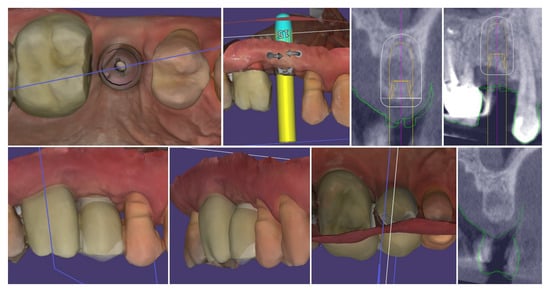

Intraoperatively, the flap preparation included (Figure 7) crestal flap preparation by marking the borders of the implantation area through the surgical guide with the tissue punch followed by crestal U-shaped incision with the blade (15C) perpendicular to crestal mucosa.

Figure 7.

Flap design and flap reflection.

The preservation of unprepared areas of the crestal soft tissue to the adjacent teeth, transformed them into the future peri-implant papillae that can be used to ensure stable primary flap closure, protecting the peri-implant bone from post-surgical resorption.

The U-shaped incision was extended mesially and distally with oblique incisions at the border of the crestal roll flap, separating the peri-implant papillae into anatomic (unprepared part) and surgical parts. The crestal part of the flap was de-epithelized with a 15C blade and microsurgical scissors and was elevated to full thickness with a periodontal chisel (36/37 Rhodes Back-Action chisel, Hu-Friedy, Chicago, IL, USA).

The buccal flap is prepared in partial thickness with the two incisions known from mucogingival surgery, described by De Sanctis and Zucchelli, a split-thickness incision, with the blade parallel to the bone, keeping the periosteum intact, and a split-thickness incision parallel to the external mucosal surface, releasing muscle insertions from the flap. A critical aspect of the procedure was the preservation of the periosteal layer on the buccal wall of the residual socket. This minimally invasive flap design, characterized by split-thickness preparation and the absence of vertical releasing incisions, ensured sufficient vascularization of the flap and minimized the risk of scar formation on the buccal surface [25,26].

The implant was placed using a digitally designed surgical guide to ensure prosthetically driven positioning. Intraoperative images demonstrate the sequence of guided placement: preparation of the osteotomy through the guide with visualization of the prepared site (left), dental implant (T3Pro, ZimVie Inc., Palm Beach Gardens, FL, USA) before placement (middle), and final implant insertion (right) with insertion torque ~50N/cm. The use of a surgical template allowed precise three-dimensional implant placement, optimal angulation, and preservation of surrounding soft and hard tissues (Figure 8).

Figure 8.

Guided implantation protocol.

The selected implant was positioned in the prosthetically driven position, with appropriate bone thickness at the buccal aspect and surrounded by healthy soft tissues (left). Another advantage of this surgical approach is the possibility to adapt the implant insertion depth corresponding to the soft tissue thickness in order to provide enough soft tissue thickness to enhance the stability of the peri-implant bone. The intraoperative measurements confirmed excellent primary stability, with ISQ values of 82 bucco-lingually and 85 mesio-distally (right). These parameters indicated optimal mechanical anchorage of the fixture within the alveolar bone, ensuring favourable conditions for osseointegration (Figure 9).

Figure 9.

Implant placement and initial stability.